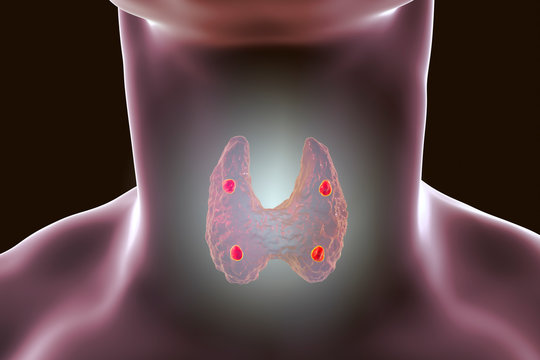

Иллюстрации и схемы по остеопорозу и паращитовидной железе